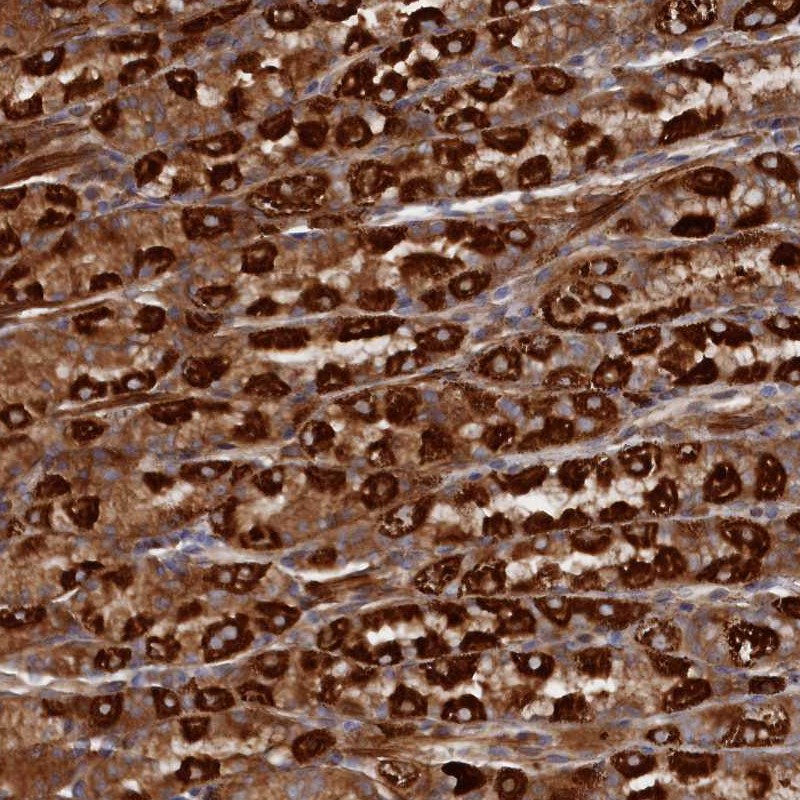

Immunohistochemical staining of human stomach, lower shows strong cytoplasmic positivity in parietal cells.